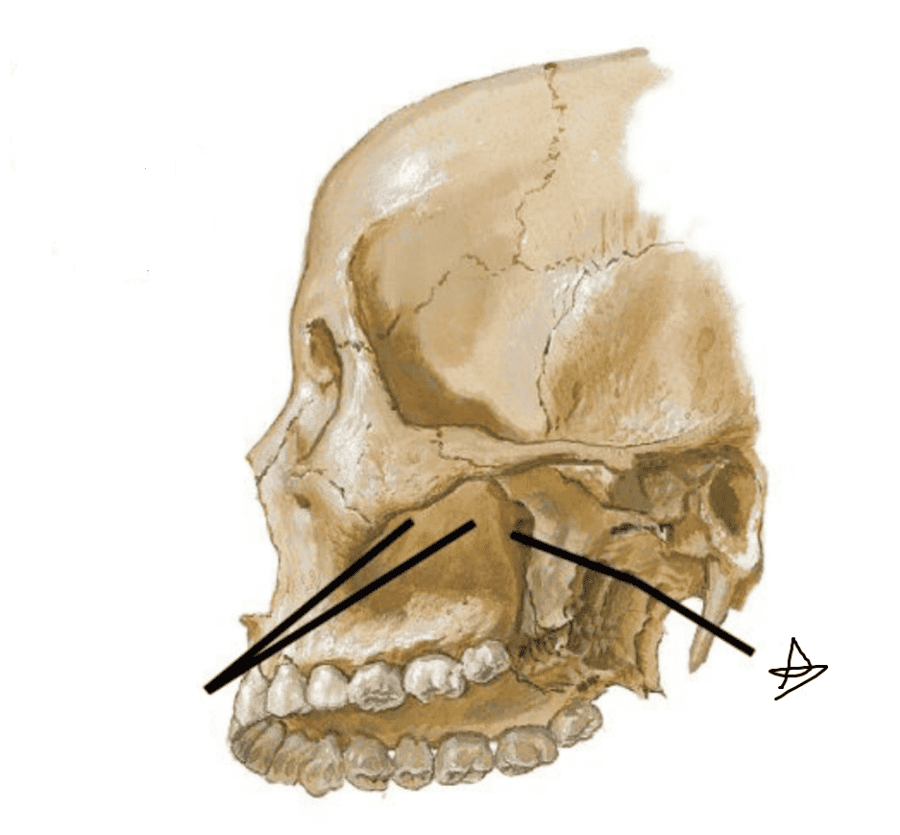

Анатомические особенности: фотографии ямок черепа, височной и подвисочной крылонебной